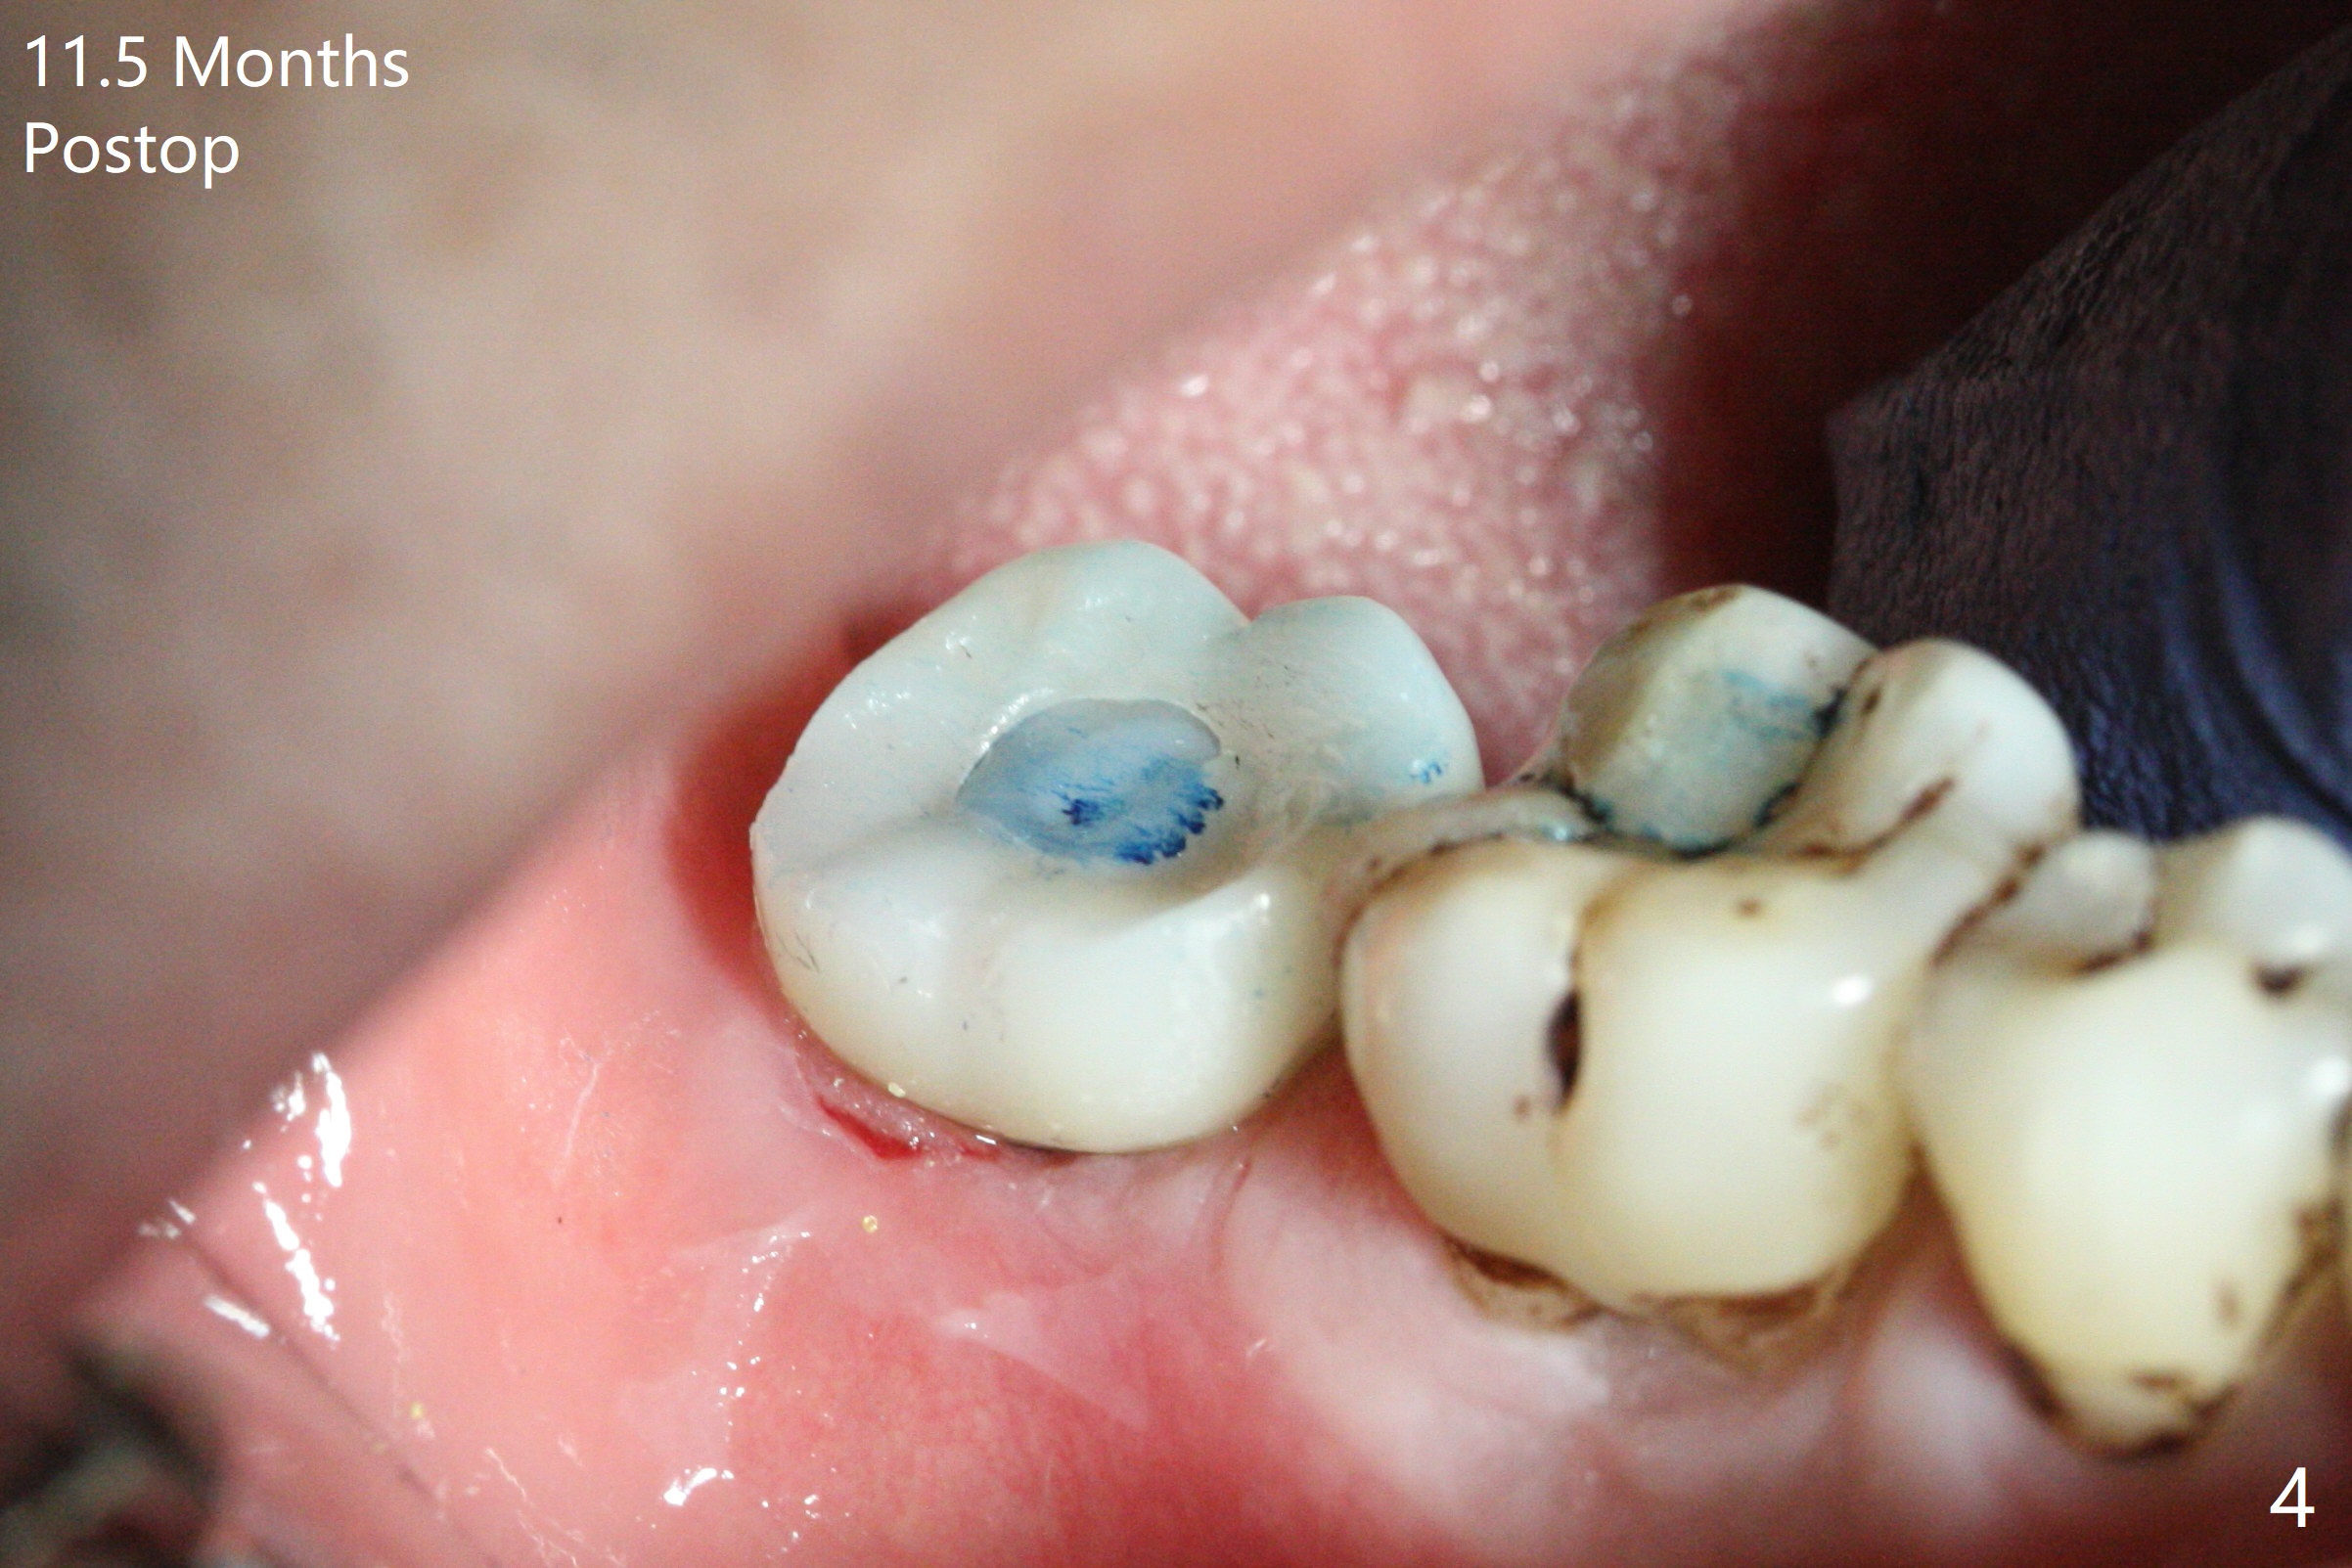

The leukoplakia at the sites of #31 and 32 is most likely related to smoking and the supraerupted teeth #1 and 2 (Fig.0 ^). After osteotomy for 11.5 mm at #31 (Fig.1), it appears that the bone height is not as much as expected. The last two drills for sequential osteotomy are 4.3x13 and 4.8x11.5 mm. A 5x11.5 mm UF implant is placed slightly subcrestal with insertion torque > 50 Ncm (Fig.2). Following placement of 6.5x2 mm healing abutment, the opposing tooth needs adjustment for height. Orthodontic intrusion of the opposing tooth is scheduled 2 days later. It is accidental to find root fracture of the mesial root of the tooth #30 (Fig.1 <). There is minimal bone resorption coronally 5 months postop (Fig.3). A provisional is fabricated at #31 to assist in intrusion of the tooth #2. A crown is cemented 11.5 months postop (Fig.4); the leukoplakia at #31 seems to lessen. The tooth #30 is lost during the pandemic, followed by looseness of the crown and abutment at #31. When the complex is reseated, the occlusal scheme is changed, suggesting incomplete seat of the abutment earlier (Fig.5).